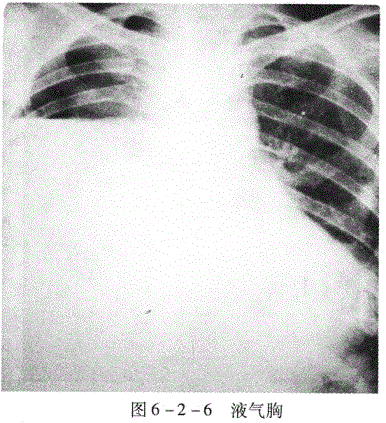

2.液气胸(图6-2-6)胸腔内液体与气体并存为液气胸。胸立位片表现为横贯胸

腔的液面,液面上方为空气及压缩的肺。气体较少时,则只见液面。

患者,男性,32岁,外伤后胸痛憋气。胸像示右侧横贯胸腔的液面,在液面上方右肺向肺门方向压缩,其与胸壁问出现透明的含气区,其内不见肺纹理,纵隔左移。